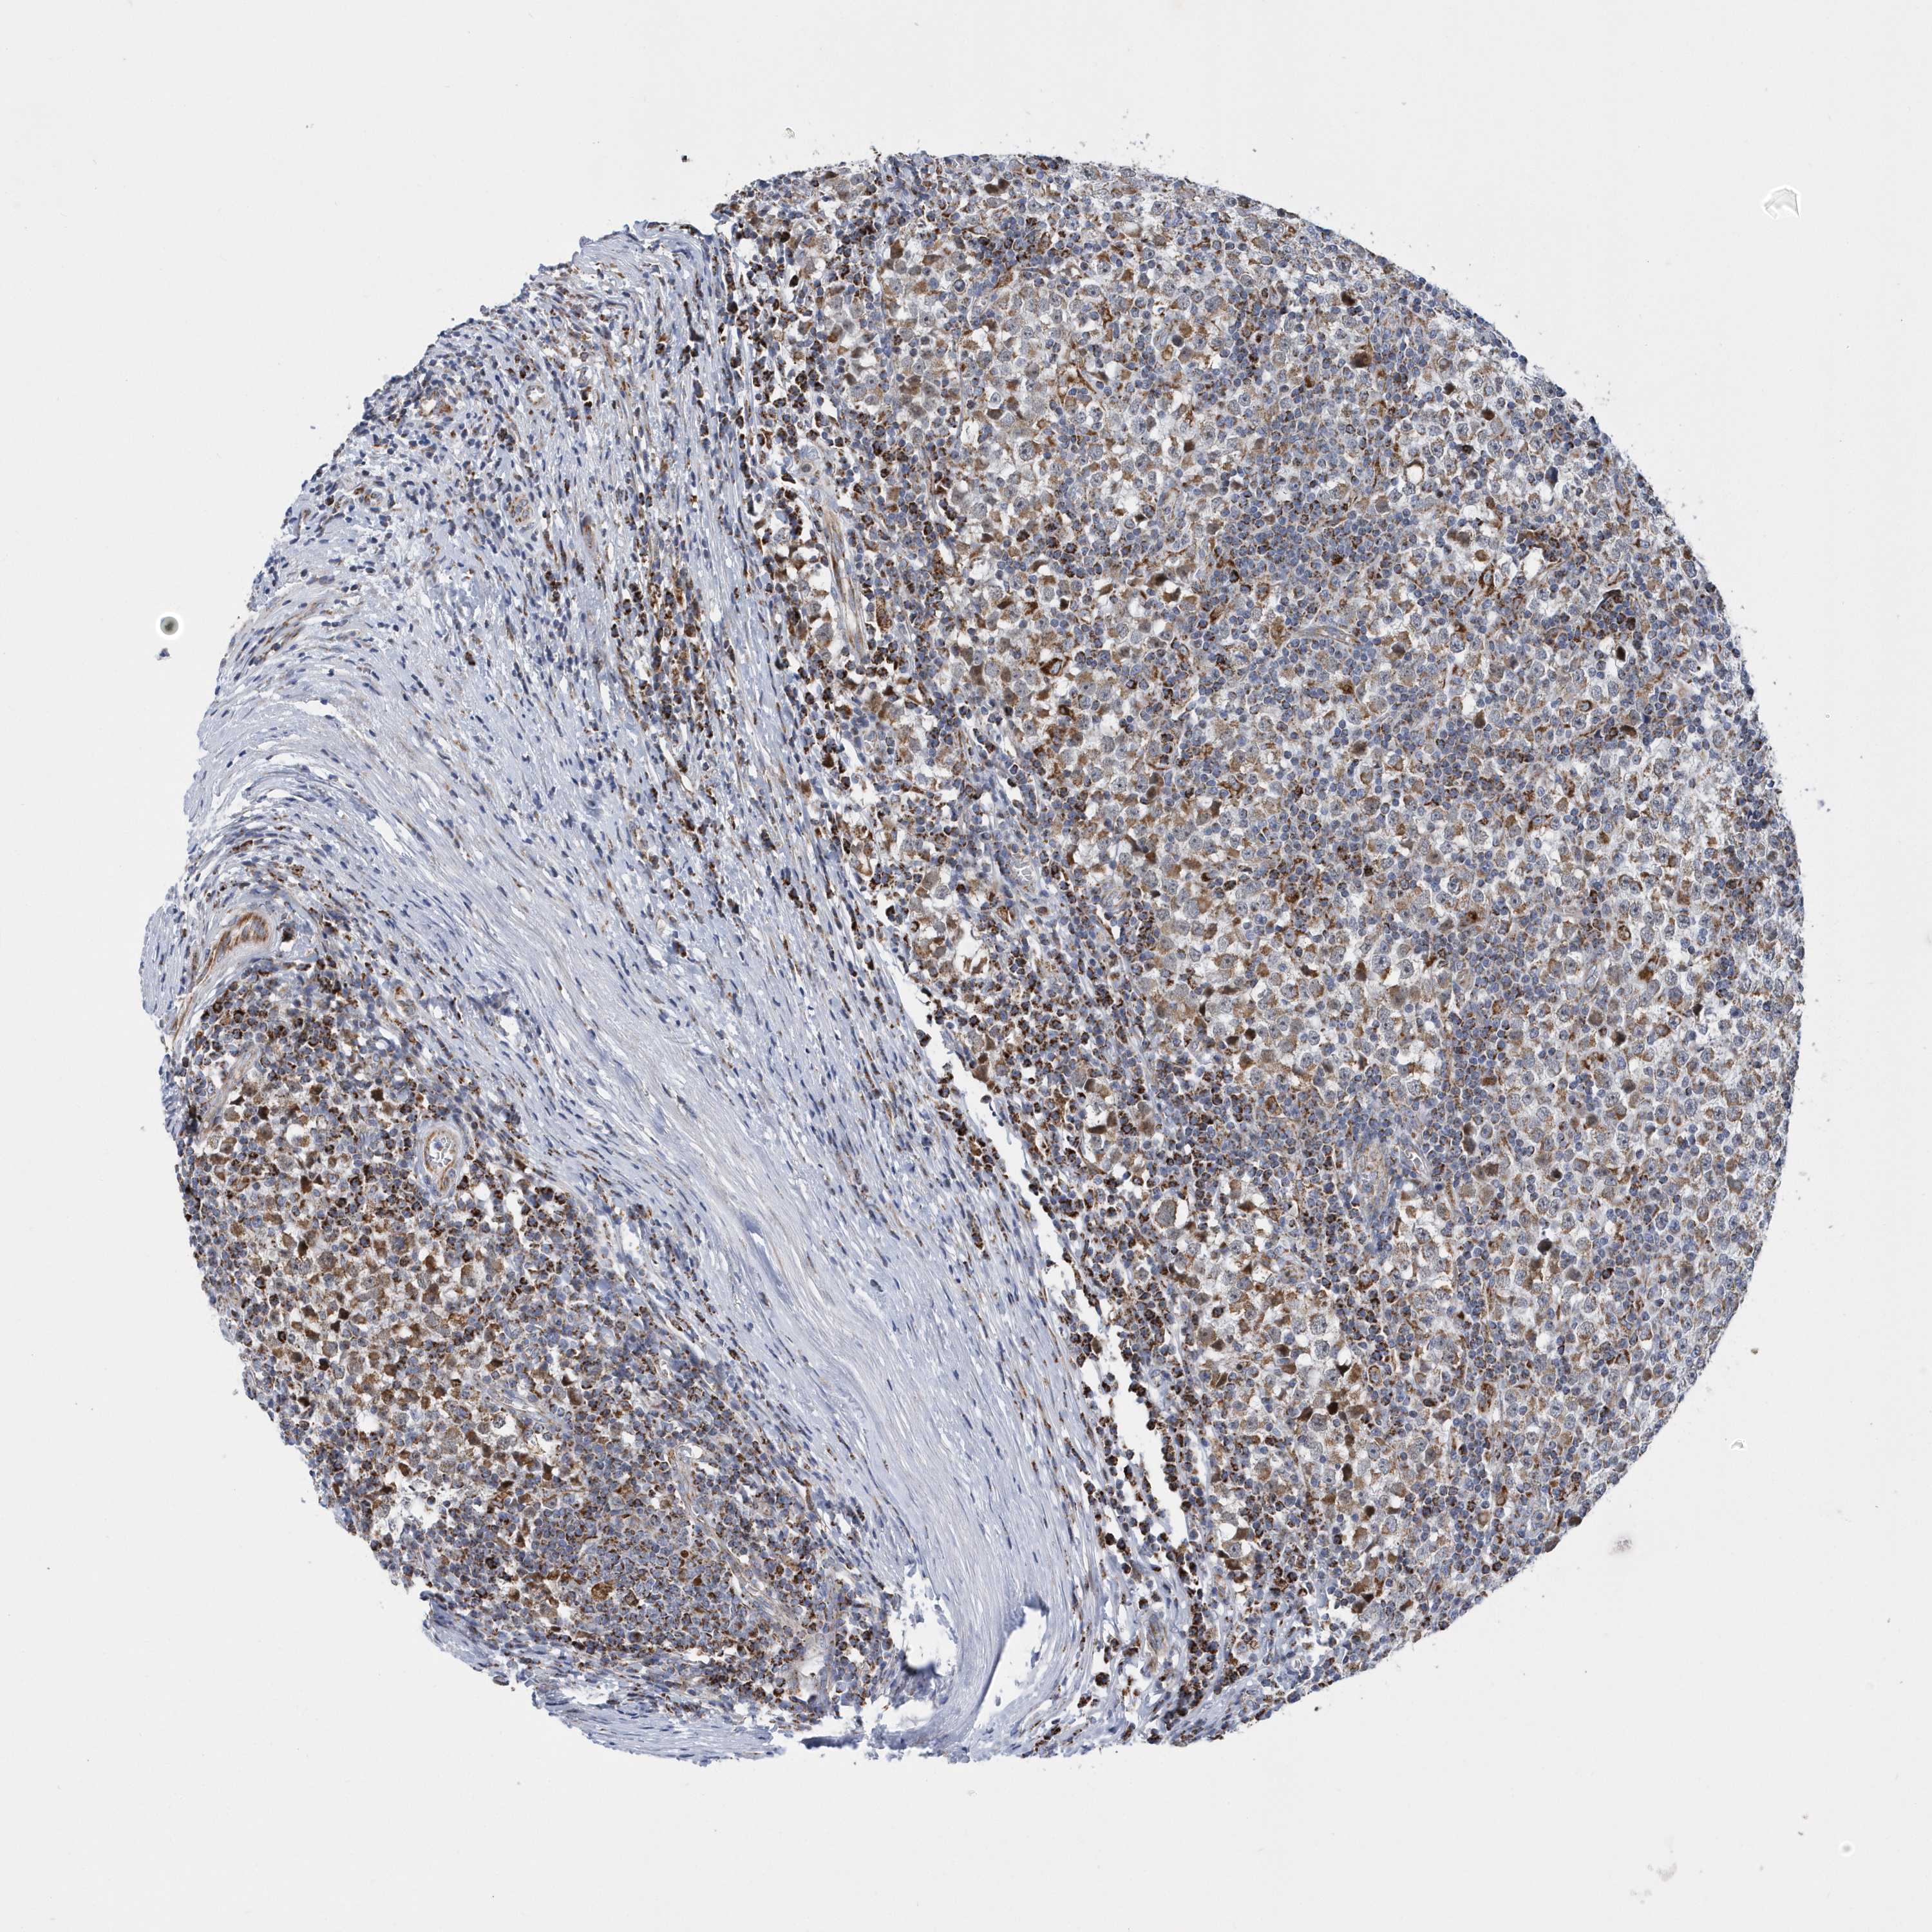

TESTIS CANCER - Protein expressioni

A mouse-over function shows sample information and annotation data. Click on an image to view it in a full screen mode. Samples can be filtered based on level of antibody staining by selecting one or several of the following categories: high, medium, low and not detected. The assay and annotation is described here.

Note that samples used for immunohistochemistry by the Human Protein Atlas do not correspond to samples in the TCGA dataset.

Antibody stainingi

Antibody staining in the annotated cell types in the current human tissue is reported as not detected, low, medium, or high, based on conventional immunohistochemistry profiling in selected tissues. This score is based on the combination of the staining intensity and fraction of stained cells.

Each image is clickable and will lead to virtual microscopy that enables deeper exploration of all samples and also displays staining intensity scores, fraction scores and subcellular localization as well as patient and tissue information for each sample.

Antibody HPA036823

Antibody HPA036824

Antibody HPA061412

Urothelial carcinoma, High grade

Teratoma, malignant, NOS